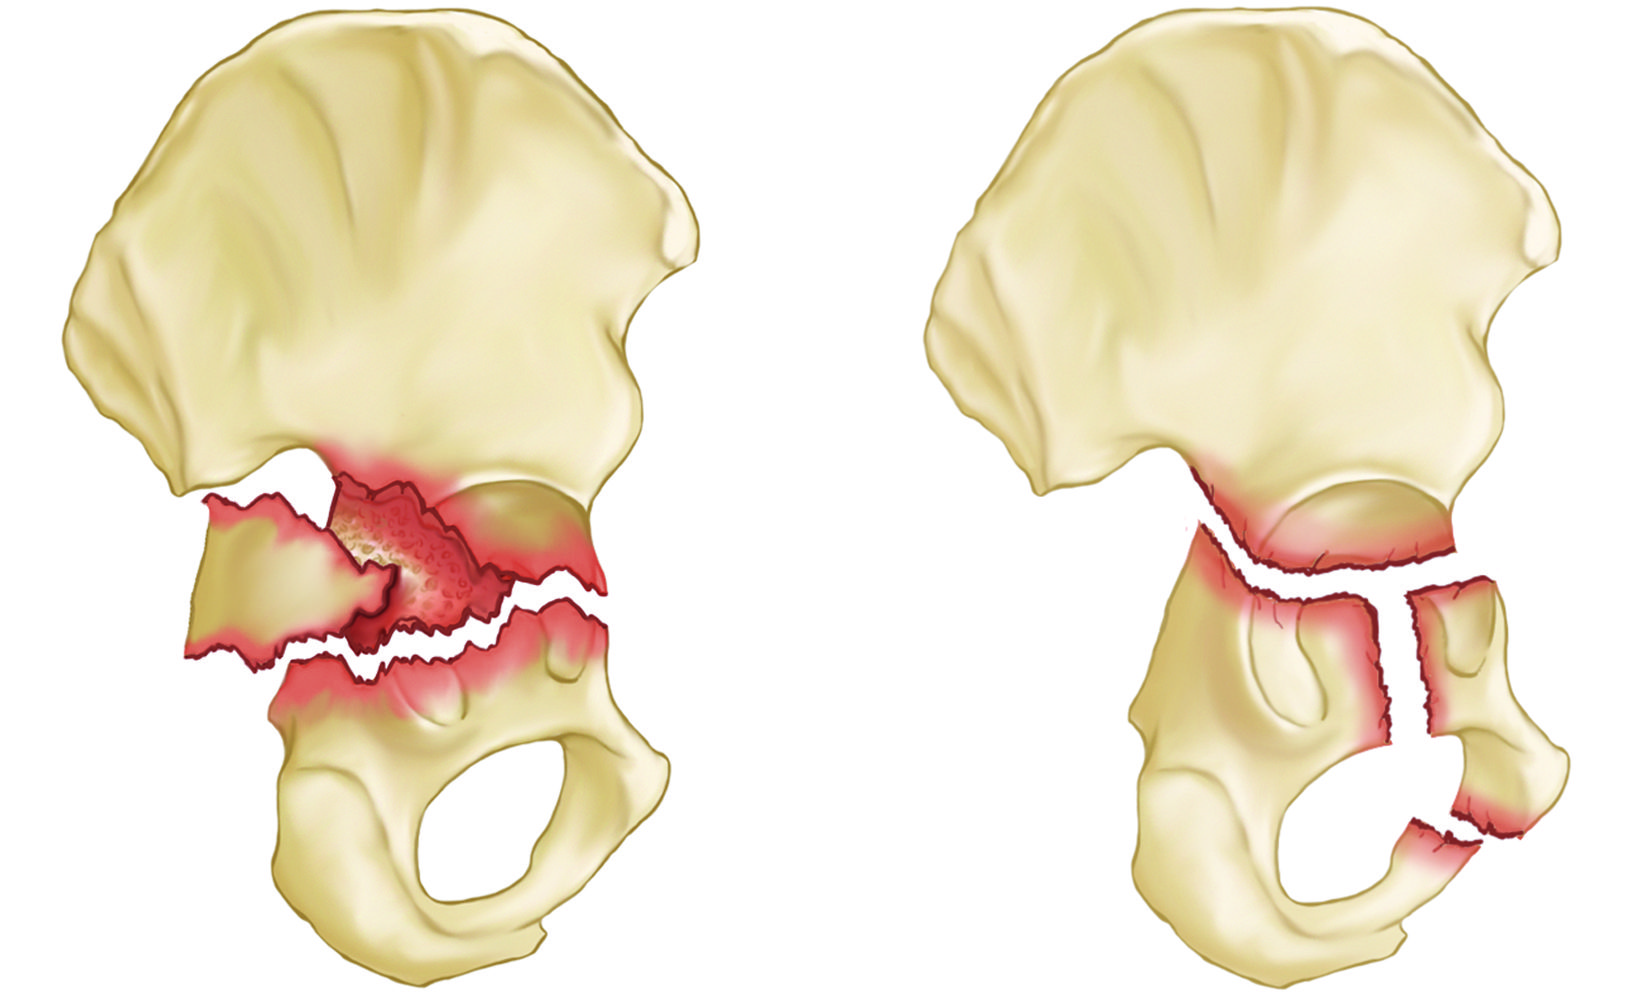

Transverse and T-shaped acetabulum fractures

(Left) Posterior wall transverse (across) fracture (Right) T-shaped fracture